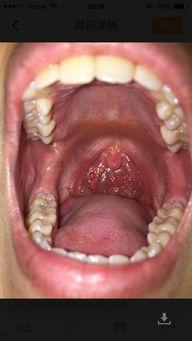

扁桃体发炎,听起来是不是就让人头疼?没错,那种喉咙痛、吞咽困难的感觉,简直让人坐立不安。据《中国中医药报》报道,扁桃体发炎是常见的呼吸道感染疾病,尤其在季节交替时更容易发生。